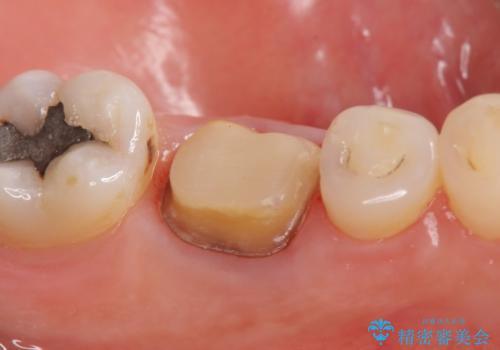

- 他院にて左下6の再根管治療を勧められ当院にいらっしゃった方の症例です。

再根管治療終了後、オールセラミッククラウンにて補綴を行いました。

- オールセラミッククラウン…¥100,000、仮歯…¥10,000、ファイバーコア…¥20,000費用は治療当時の料金となります